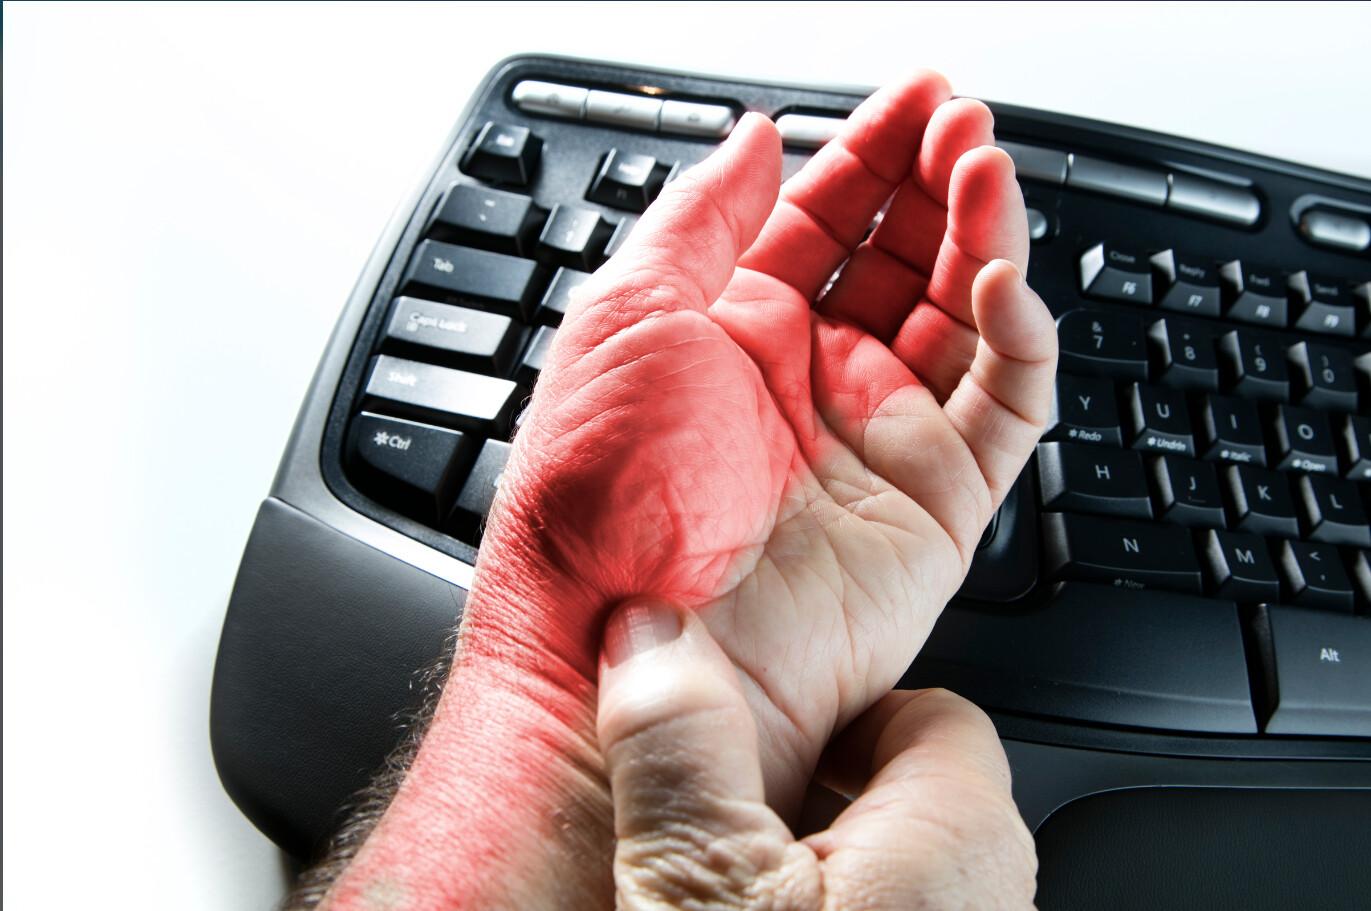

Az alagút szindróma az ideg- és szöveti összenyomódás következtében alakul ki. A csontok és lágyrészek...